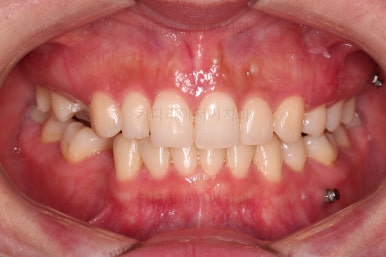

장치 착용 모습인데요.

교정 중임에도 불구하고 거의 눈에 띄지 않는다는 압도적인 장점이 있죠.

공간, 교합, 중앙선 모두 매우 좋아지고 있습니다.

중앙선도 처음보다 매우 좋아진 양상입니다.